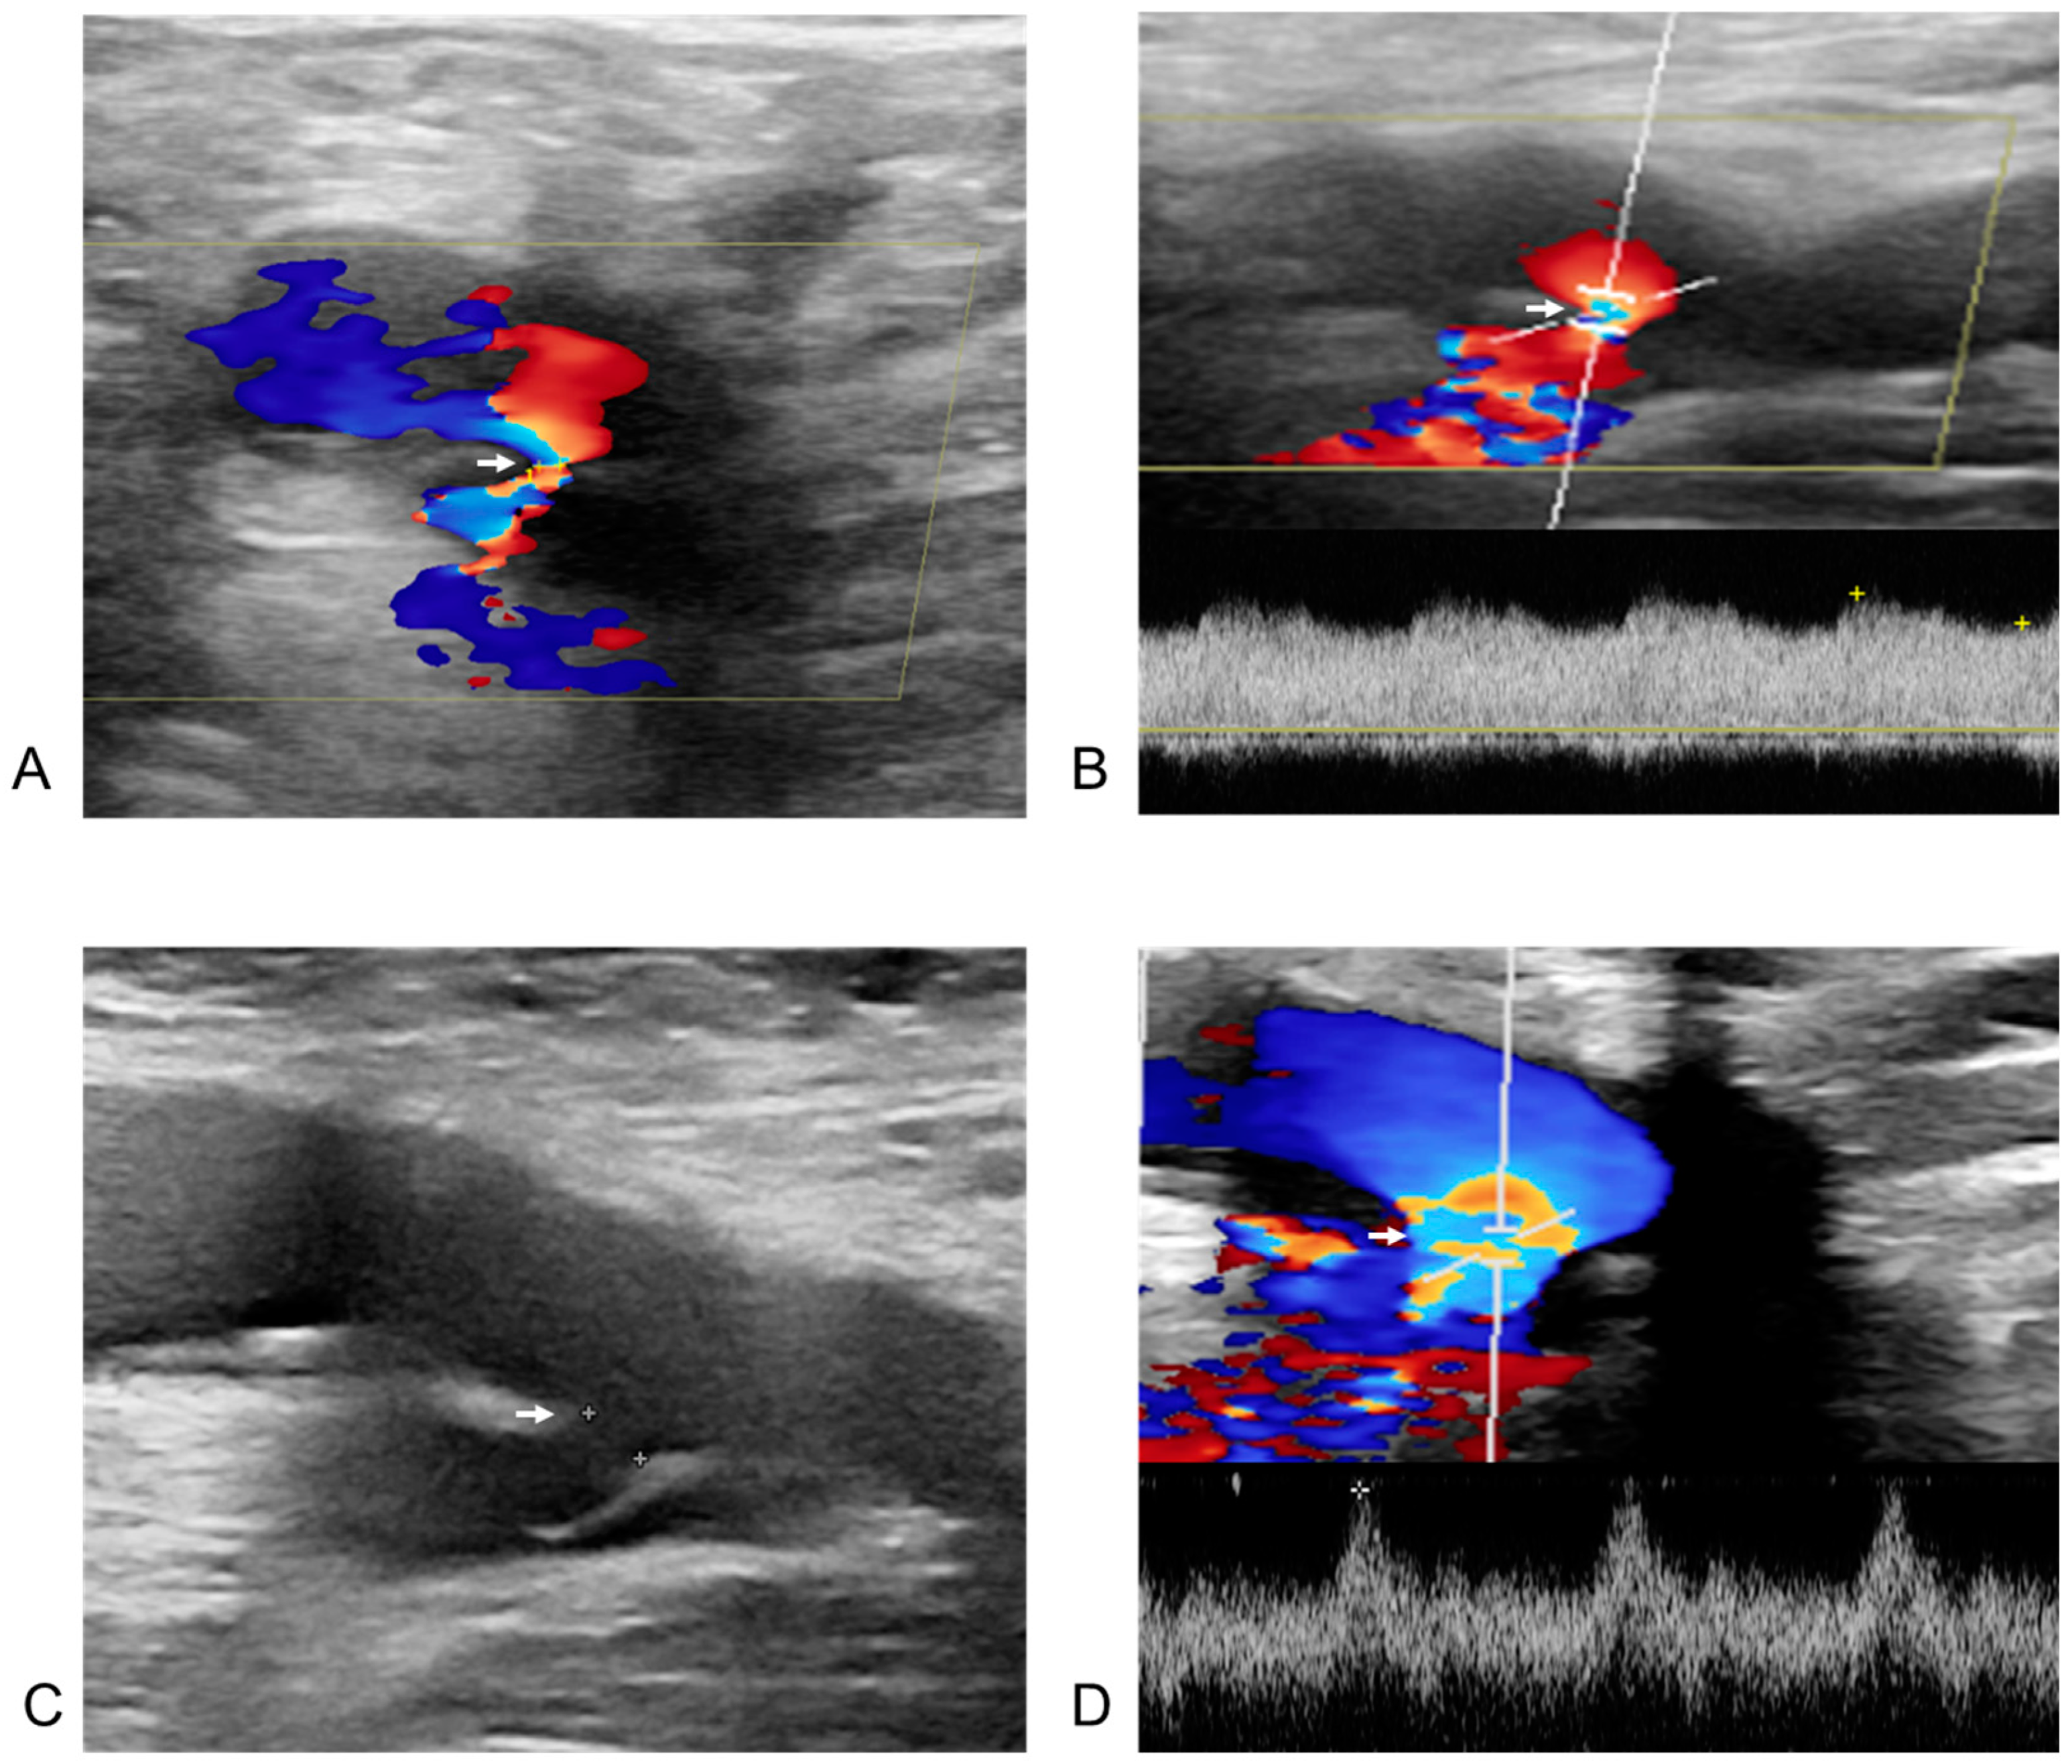

3.4. Management of Femoral Vascular Complications